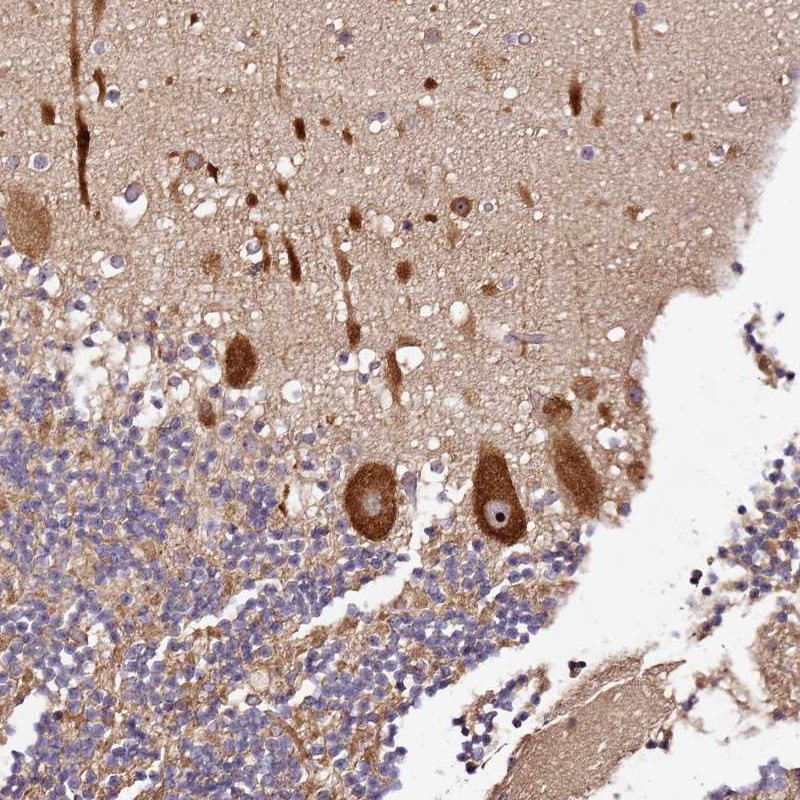

Immunohistochemical staining of human cerebellum shows strong nucleolar and cytoplasmic positivity in Purkinje cells.